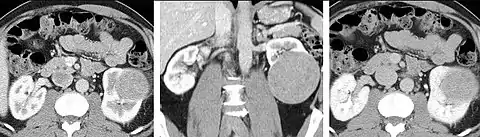

The late arterial phase is timed to correspond to the peak concentration of contrast material in highly vascular tumors and is performed approximately 20–35 seconds after the injection of intravenous contrast. Early arterial phase imaging is predominantly utilized for angiography and will be discussed separately. Late arterial phase imaging is almost always performed in conjunction with other phases (e.g. portal venous phase) to allow more complete characterization of any identified abnormalities (figure 4). The primary indication for a late arterial phase is for the evaluation of hypervascular tumors of the liver such as hepatocellular carcinoma or hypervascular metastases (figure 4). Typical hypervascular tumors for which this would be used include: hepatocellular carcinoma; renal cell carcinoma; melanoma; carcinoid/neuroendocrine tumors; some sarcomas; choriocarcinoma; and thyroid carcinoma. Although a “hypervascular”, biphasic evaluation would generally be used for these patients, note that a single phase is often adequate for follow up imaging.

When evaluating hepatic masses, it can be advantageous to have both late arterial and portal venous phase images (biphasic imaging, figure 4) since some tumors enhance briskly during the arterial phase (hepatocellular carcinoma, hepatic adenoma, follicular nodular hyperplasia (FNH), and hypervascular metastasis), but may be occult or difficult to characterize on portal venous phase imaging alone (figure 6). However, it should be stressed that the addition of late arterial phase images is only indicated if one of these tumors is suspected, or if there is a need for further characterization of a hepatic mass, since the large majority of patients will not benefit from the addition of this phase. In addition, if there is a need to definitively characterize a hepatic mass, MRI is generally more sensitive and specific, with no associated radiation dose.

Pancreatic masses are often evaluated using both an early arterial (to evaluate for vascular involvement and thus resectability, figure 9a) and a later “pancreatic” phase (which optimizes pancreatic parenchymal enhancement and thus is best at differentiating pancreatic tumors from pancreatic parenchyma, figure 9b). Pancreatic adenocarcinoma typically is hypoenhancing when compared to the surrounding parenchyma. Most other common pancreatic tumors are hypervascular with avid enhancement (such as pancreatic neuroendocrine tumors) and appear brighter than the surrounding pancreatic parenchyma after the injection of intravenous contrast material.